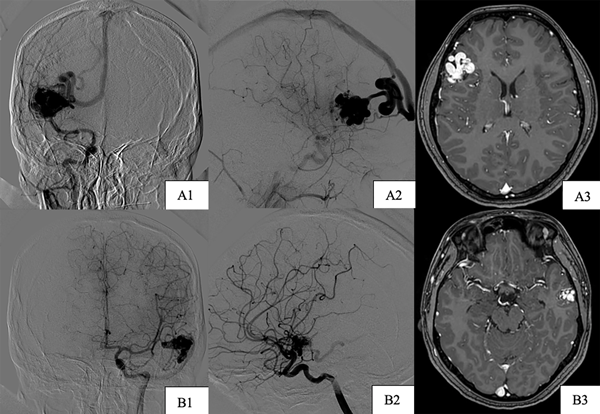

Paciente de sexo femenino, de 17 años, sin antecedentes patológicos, a quien en contexto de estudio por episodio de crisis comiciales de novo se le diagnostican dos MAVs supratentoriales, una frontal derecha de 25 x 29 mm diámetro, con aferencias silvianas, de nido compacto y drenaje hacia el seno longitudinal superior a través de gran vena cortical y otra temporal izquierda de 16 x 11 mm con aferencias silvianas, de nido compacto y drenaje hacia el seno transverso, sin evidencia de signos sugestivos de sangrado (Figura 4). Se decidió estudiar y descartar síndromes congénitos para luego programar la cirugía. Debido a que ninguna de las dos lesiones presentaba factores angiográficos de rotura y por su localización en el hemisferio no dominante se decidió abordar inicialmente la malformación frontal derecha (Figura 5) y 7 meses después se realizó la exéresis de la restante con control angiográfico postquirúrgico satisfactorio y ninguna complicación asociada (Figura 6).

Figura 4. Imágenes preoperatorias caso 2. A) MAV frontal derecha. A1) Incidencia frente. A2) Incidencia perfil. A3) Incidencia axial de RM. B) MAV temporal izquierda. B1) Incidencia frente. B2) Incidencia perfil. B3) Incidencia axial RM.